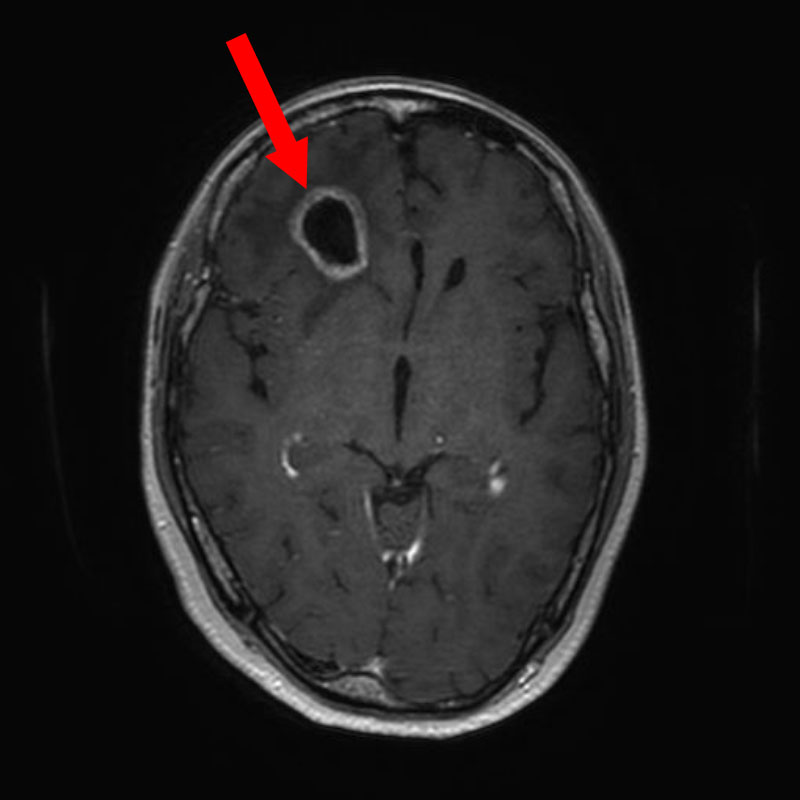

620

'25年4月

60代

円蓋部髄膜腫

頭蓋内腫瘍摘出術

No.’25_22 手術前1

No.’25_22 手術前2